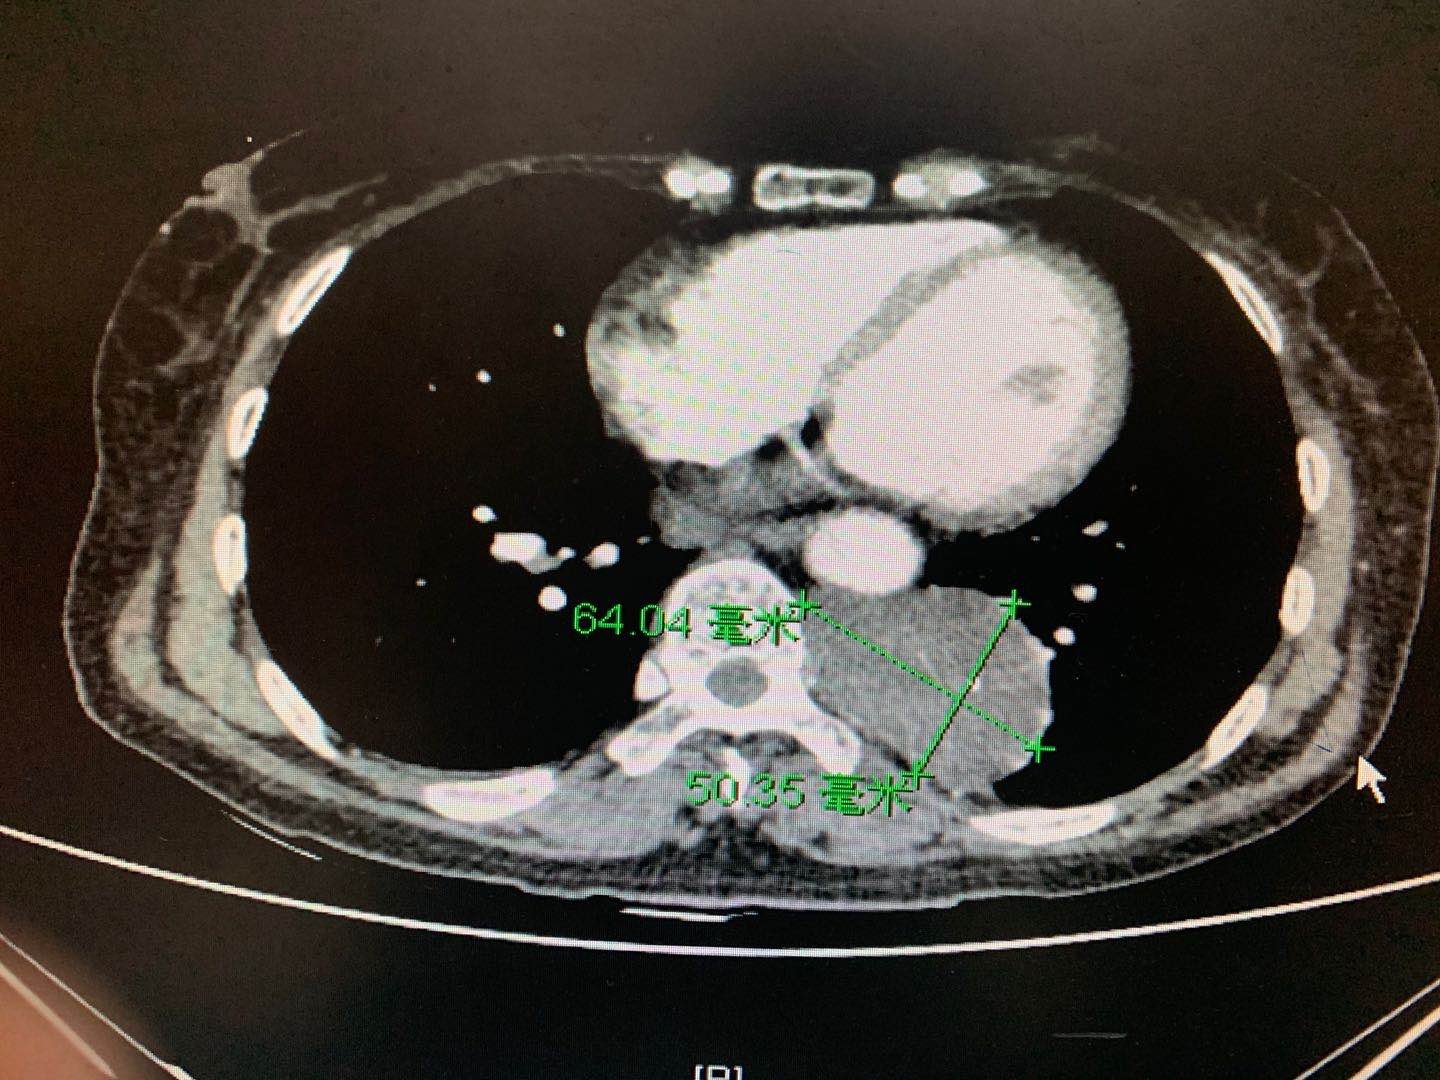

近日,徐醫(yī)附院心胸外科王國(guó)祥、侯永波、張虎團(tuán)隊(duì)在麻醉科及手術(shù)室的幫助下,成功為一例較大縱膈腫瘤患者實(shí)施了達(dá)芬奇機(jī)器人輔助行胸腔鏡下手術(shù)切除。該縱膈腫瘤位于胸主動(dòng)脈和椎體之間,6.4cm×5.0cm大小,且和椎間神經(jīng)與血管相連。手術(shù)團(tuán)隊(duì)通過(guò)充分發(fā)揮手術(shù)機(jī)器人的優(yōu)勢(shì),在狹小的空間里,在10倍放大的視野下實(shí)施精準(zhǔn)操作,不僅成功地完整地切除了腫瘤,還避免了對(duì)周圍組織的損傷。